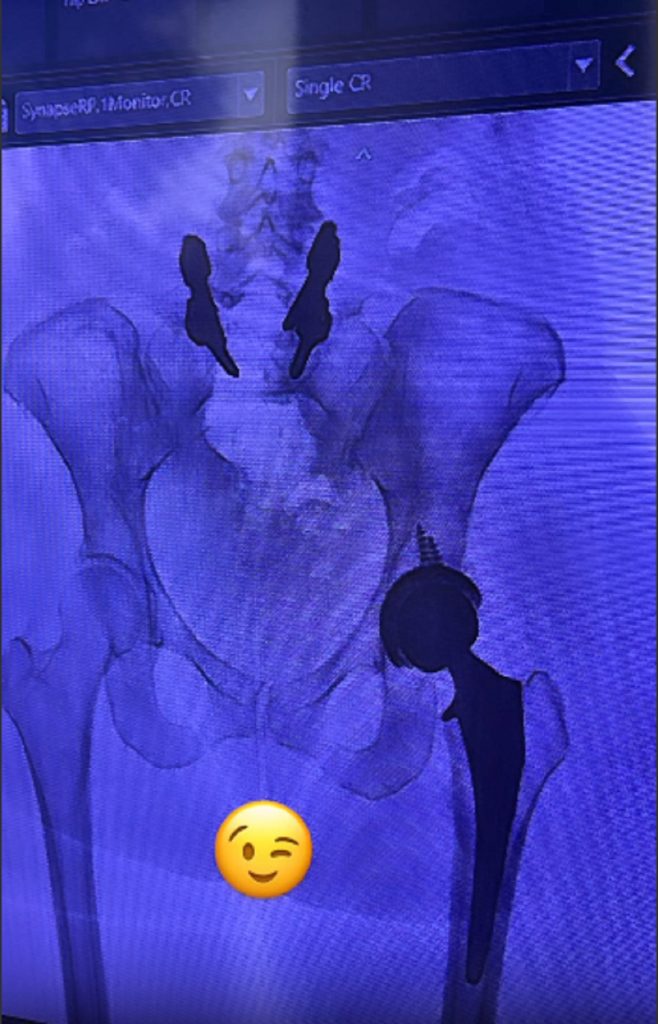

María Alejandra Requena reveló que se sometió recientemente a una cirugía de reemplazo total de cadera. La comunicadora y presentadora venezolana destacó que con este procedimiento busca mejor su calidad de vida y evitar el dolor que la venía afectado en meses recientes.

“Vine defectuosa de fábrica  ¿Qué les puedo decir? Quizás esa es la explicación más sencilla, y es que cuando tenía 18 años recién cumplidos tuve que operarme de la columna y ahora me tocó hacer reemplazo total de la cadera izquierda”, contó la autora del libro ‘Elijo ser feliz’ en su perfil de Instagram.

Requena, que se dio a conocer en Venezuela en 1998 en el programa de RCTV ‘Atrévete a soñar’ , contó en el texto que comenzó a tener problemas con la articulación luego de que hace nueve meses hiciera un movimiento brusco mientras realizaba un ejercicio. Ese incidente provocó que se rompiera el labrum (anillo de tejido blando) que protege la articulación de la cadera.

“Fue entonces cuando descubrimos que nací con displasia de cadera severa (que fue lo que originó el desgaste del labrum)”, reveló.